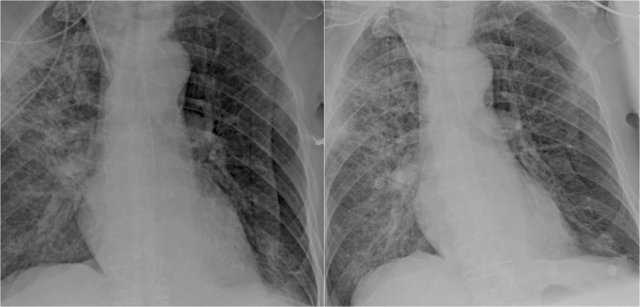

It is extremely important to always compare with old films, as we will demonstrate in this case.

Actually someone said that the most important radiograph is the old film, since it gives you so much information.

For instance a lung mass, which hasn't changed in many years is not a lung cancer.

Based on these films, you could make the diagnosis of congestive heart failure, but the findings are subtle.

Scroll back and forth to the old film.

Once you compare the chest film to the old one, things become more obvious and you will be much more confident in your diagnosis of congestive heart failure:

- The size of the heart is slightly increased compared to the old film, but was already large on the old film.

- The pulmonary vessels are slightly increased in diameter indicating increased pulmonary pressure.

- There are maybe some subtle interstitial markings as a result of interstitial edema.

- There is pleural fluid bilaterally. Notice that the infero-posterior border of the lower lobes has changed in position.